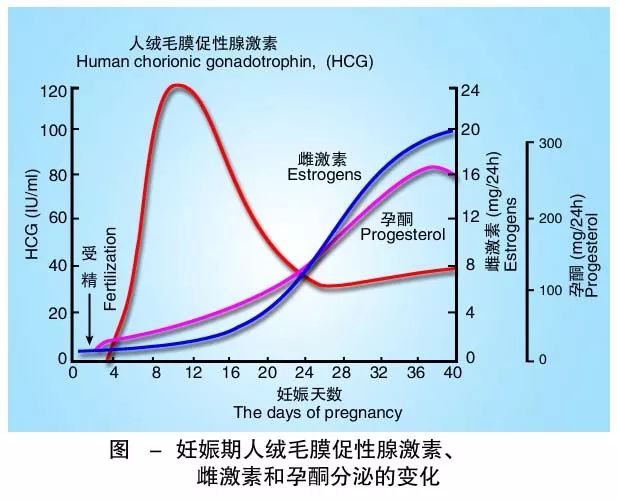

HCG在妊娠診斷、生育輔助中的作用

發布日期:2023-08-28

人類絨毛膜促性腺激素(Human Chorionic Gonadotropin,簡稱hCG)是一種重要的激素,對于人類的生殖系統和妊娠過程起著關鍵作用。它是一種由胚胎發育過程中形成的蛋白質激素,最 卵泡刺激素:更年期女性身體和心理健康的關鍵

HCG和孕酮有什么關系?它們有什么功能與生理作用?

發布日期:2023-07-19

HCG和孕酮是兩種與妊娠相關的激素,它們在妊娠期間的變化對胎兒的發育和母體的健康都有重要的影響。本文將詳細介紹HCG和孕酮的定義、功能、生理作用、測量方法以及它們之 FSH特別高做試管能成功嗎

人絨毛膜促性腺激素低對保胎的影響

發布日期:2023-09-26

人絨毛膜促性腺激素(hCG)是一種由合體滋養層細胞產生的激素,對妊娠的維持至關重要。然而,某些情況下,患者可能會出現人絨毛膜促性腺激素低的情況,這可能導致妊娠的不良結局,如 關注更年期健康:女性需知的重要事項

懷孕期間HCG低怎么辦?

發布日期:2023-05-09

人絨毛膜促性腺激素(human choionic gonadotophin,HCG)是婦產科醫生們所熟悉和最常使用的“妊娠試驗”激素。 它是胎盤的滋養層細胞所分泌的一種糖蛋白激素 女性在排卵當天有哪些癥狀